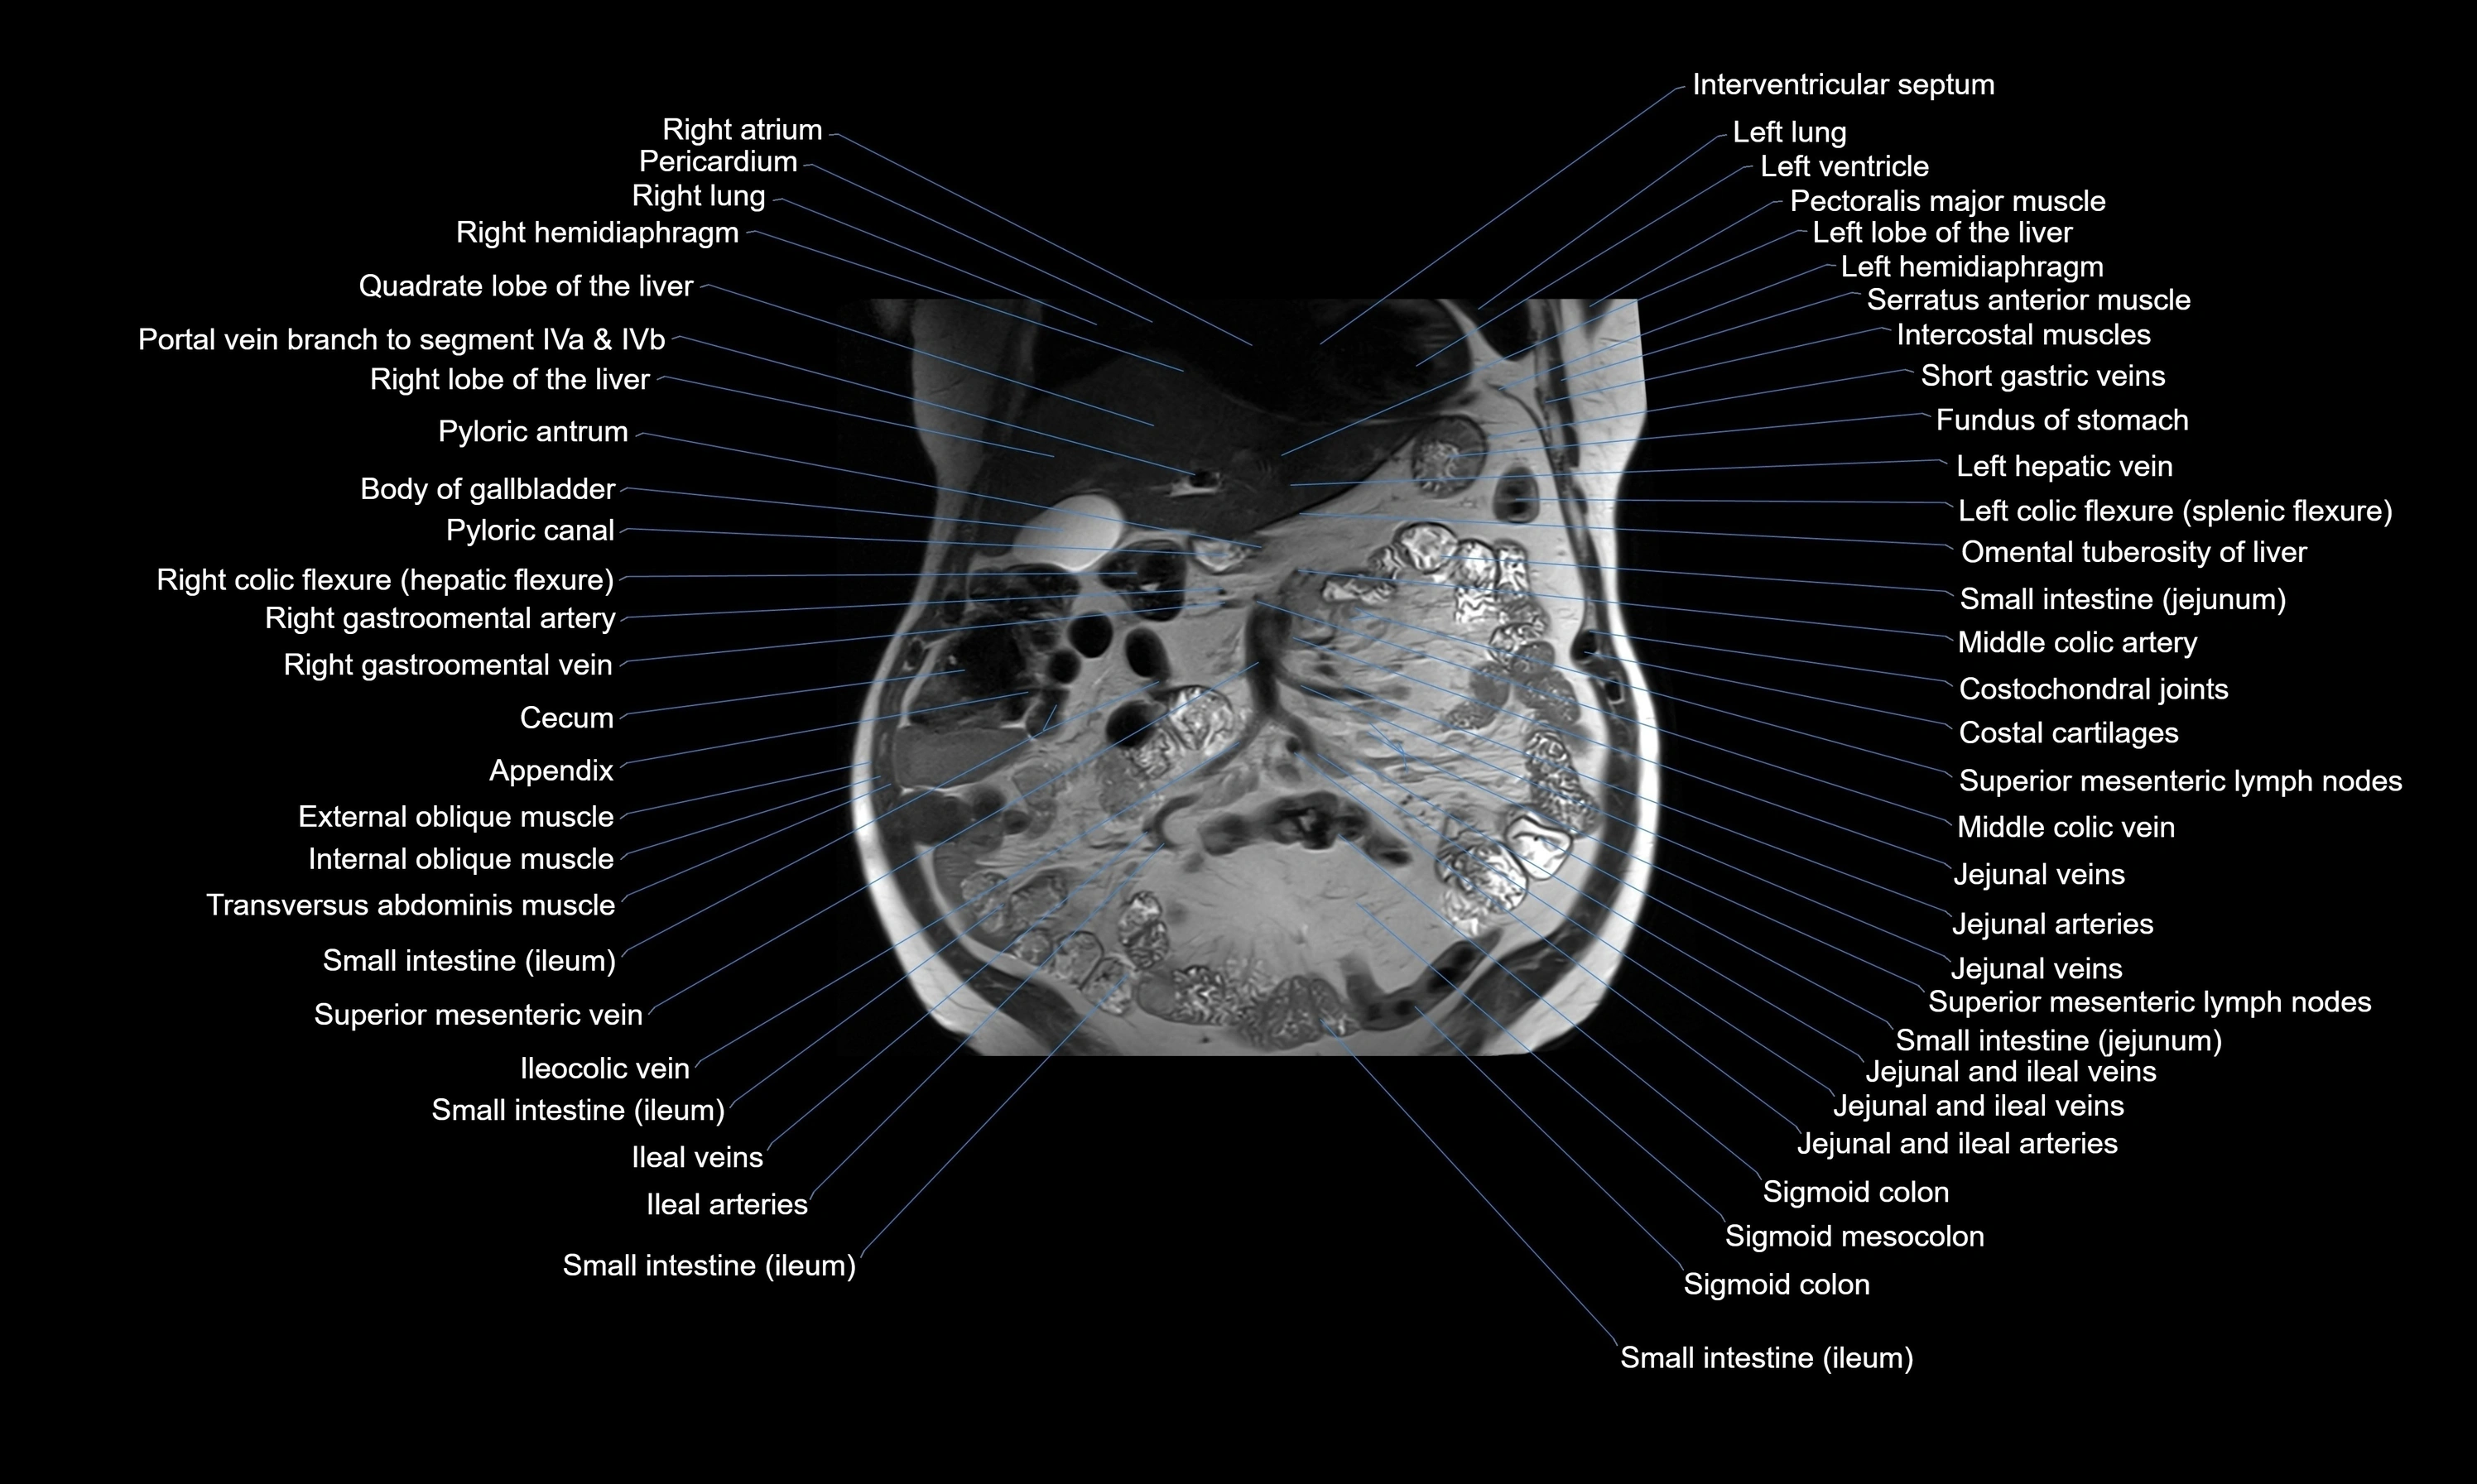

MRI images